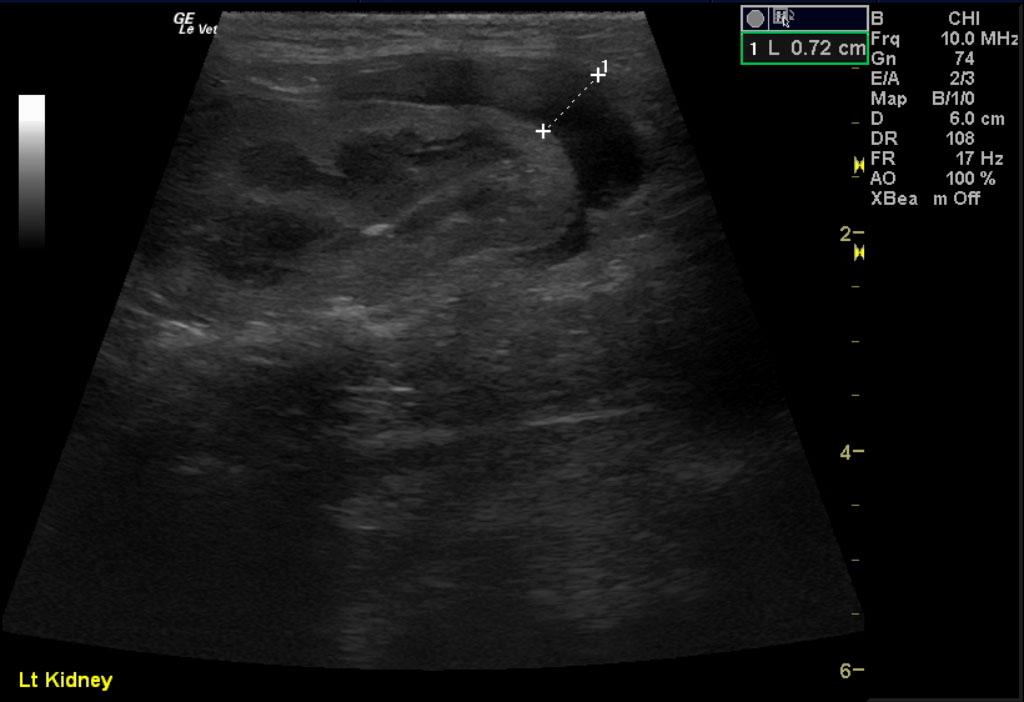

Image 1 & Video 1: The liver was moderately enlarged, rounded in shape having mildly hypoechoic echogenicity with multifocal hypoechoic and cystic nodules throughout. The gallbladder was normal in size, shape, and clean. Images 2-4 & Video 2-4: The left and right kidneys were severely enlarged with mild hydronephrosis in the right kidney. Both kidneys had hyperechoic cortices with large hypoechoic caps surrounding and invading the renal cortices (left kidney cap-7.4 mm in thickness, right kidney cap-13.6 mm in thickness). Image 5 & Video 5: Stomach: mucosal layer is mild/moderately thickened with overall wall thickness measuring 3.8 mm. Images 6: Intestine: there is focal mucosal layer thickening measuring up to 5.1 mm while the rest of the intestinal loops are of normal thickness. Video 6: Colon: the colonic wall appeared thickened at the ileocecolcolic junction. Image 7: Lymph Nodes: Multiple mesenteric lymph nodes were severely enlarged throughout the abdomen. The epigastric LN enlargement is shown in this image in the near field.